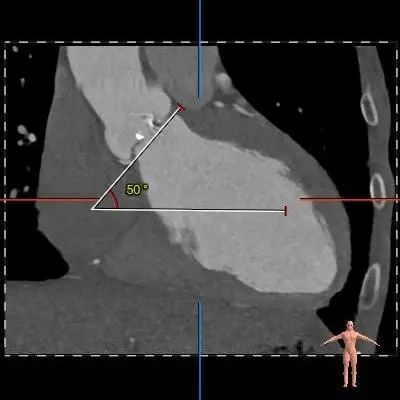

术前CT评估

4.左冠开口高度可,右冠风险较高。

冠脉阻挡风险及左室大小评估